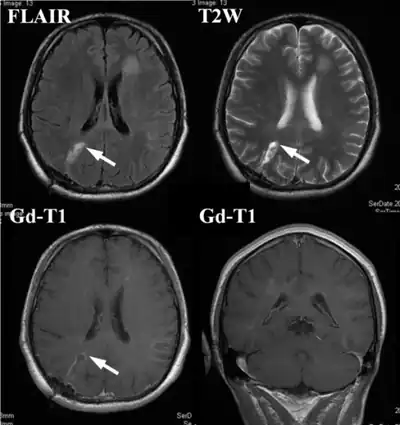

An example of a ring-enhancement around a lesion in gliobastoma. In tumefactive multiple sclerosis, the ring-enhancement is open, not forming a complete ring.

These atypical lesion characteristics include a large intracranial lesion of size greater than 2.0 cm with a mass effect, edema and an open ring enhancement. A mass effect is the effect of a mass on its surroundings, for example, exerting pressure on the surrounding brain matter. Edema is the build-up of fluid within the brain tissue. Usually, the ring enhancement is directed toward the cortical surface.[2] The tumefactive lesion may mimic a malignant glioma or cerebral abscess causing complications during the diagnosis of tumefactive MS. T2-hypointense rim and incomplete ring enhancement of the lesions on post-gadolinium T1- weighted imaging on brain MRI enable accurate diagnosis of TDL[3]

Diagnosis of tumefactive MS is commonly carried out using magnetic resonance imaging (MRI) and proton MR spectroscopy (H-MRS). Diagnosis is difficult as tumefactive MS may mimic the clinical and MRI characteristics of a glioma or a cerebral abscess. However, as compared to tumors and abscesses, tumefactive lesions have an open-ring enhancement as opposed to a complete ring enhancement.[1] Even with this information, multiple imaging technologies have to be used together with biochemical tests for accurate diagnosis of tumefactive MS.[36]

MRI diagnosis is based on lesions that are disseminated in time and space, meaning that there are multiple episodes and consisting of more than one area.[39] There are two kinds of MRI used in the diagnosis of tumefactive MS, T1-weighted imaging and T2-weighted imaging. Using T1-weighted imaging, the lesions are displayed with low signal intensity, meaning that the lesions appear darker than the rest of the brain. Using T2-weighted imaging, the lesions appear with high signal intensity, meaning that the lesions appear white and brighter than the rest of the brain. When T1-weighted imaging is contrast-enhanced through the addition of gadolinium, the open ring enhancement can be viewed as a white ring around the lesion.[40] A more specific MRI, Fluid attenuation inversion recovery (FLAIR) MRI show the signal intensity of the brain. Subjects with tumefactive multiple sclerosis may see a reduction of diffusion of the white matter in the affected area of the brain.[11]

High-intensity areas shrink after 1 month of steroid management ( Gd-enhanced lesions completely disappear), arrow(s) indicate biopsy points